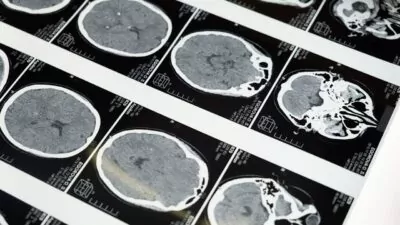

Utilizando exames de imagem e critérios clínicos rigorosos, eles identificaram alterações estruturais que podem estar relacionadas a comportamentos impulsivos e à falta de empatia.

O estudo analisou o cérebro de 39 homens, sendo parte deles diagnosticados com traços psicopáticos. Foram utilizadas imagens de ressonância magnética estrutural, além de uma ferramenta clínica especializada para mensuração dos níveis de psicopatia. Esse método possibilitou a comparação precisa entre os dois grupos e revelou mudanças específicas na anatomia cerebral associadas a esse distúrbio de personalidade.

Os resultados indicaram uma redução média de 1,45% no volume cerebral dos indivíduos com traços psicopáticos, especialmente em áreas associadas ao controle emocional e tomada de decisão. Essas alterações foram mais pronunciadas em características ligadas à impulsividade e comportamento antissocial, e menos em aspectos como manipulação ou frieza emocional.